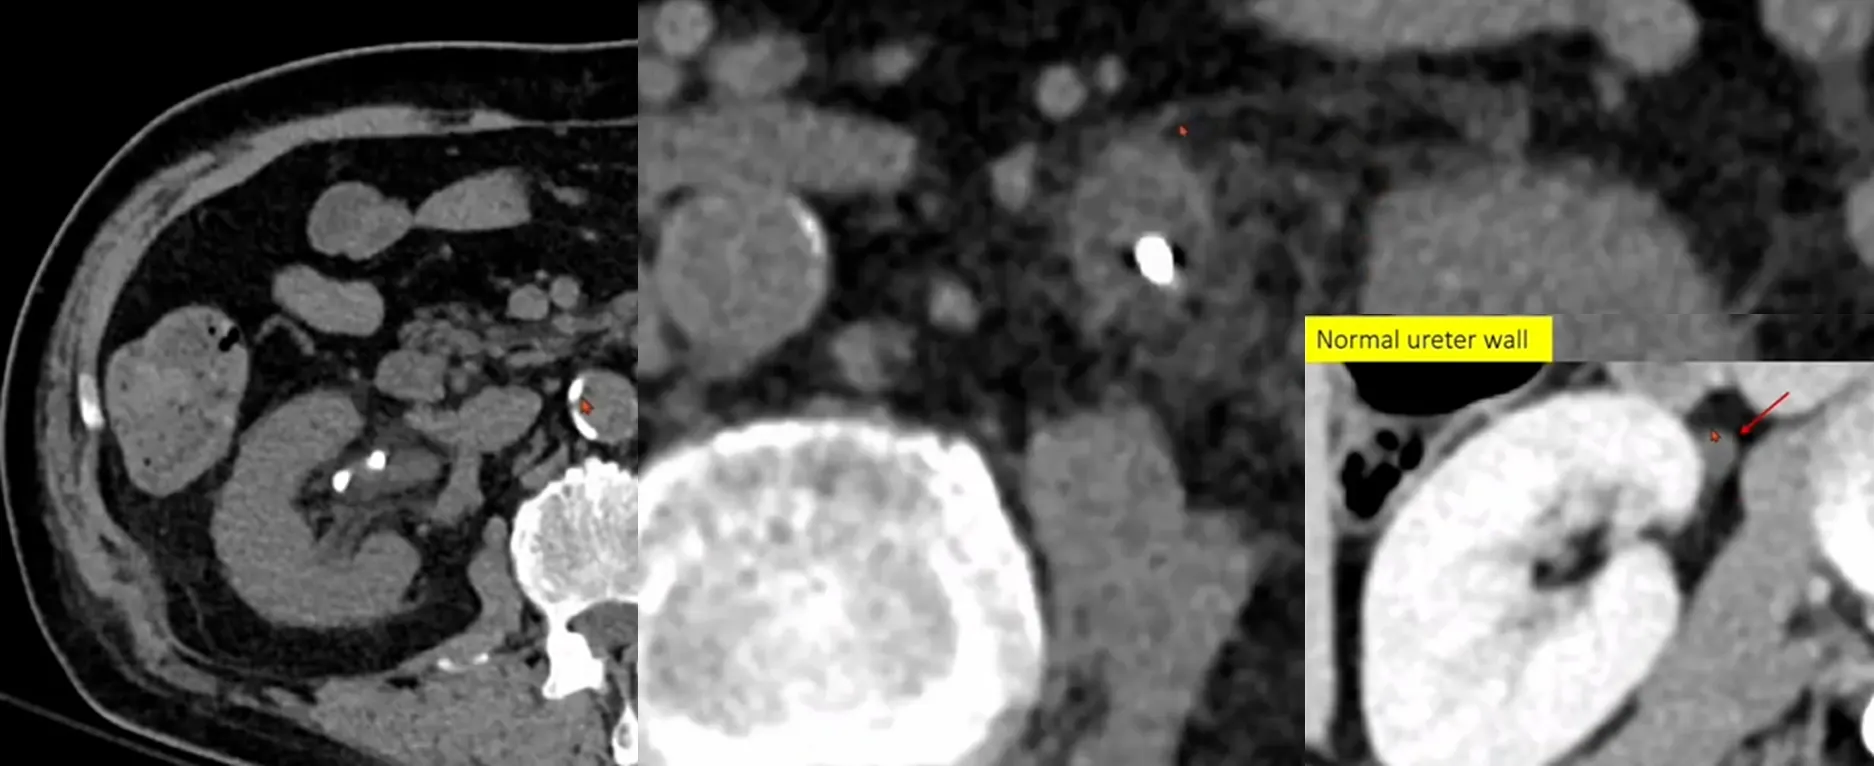

Case 10-2

•

M/43

C/C: Abdominal pain, aggravation

Hx : h/o ureter stone

Lab: within normal limit